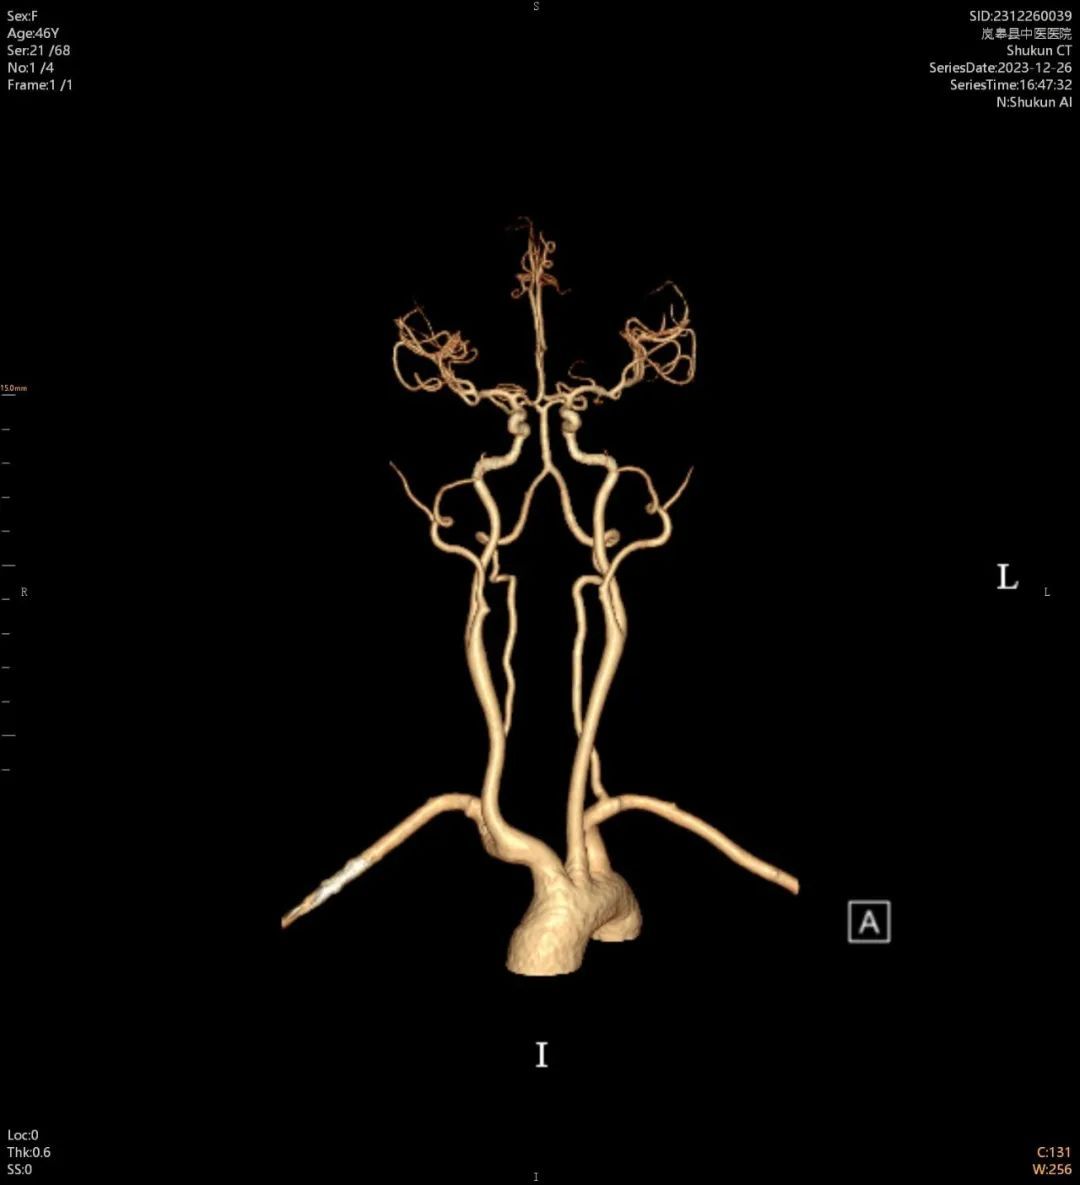

近日,在西安市中医脑病医院派驻的影像科专家任小军的指导下,岚皋县中医医院放射科成功开展了首例CT增强扫描及CT血管造影(CTA)新技术,填补了该院影像技术上的一项空白,提升了疑难疾病的诊断能力。

患者何某,患有“主动脉瓣关闭不全”,活动后感觉“胸闷、胸痛”,心电图检查提示“心肌缺血”,经CT血管造影(CTA)检查后,诊断更加明确,为“壁冠状动脉(心肌桥)”,排除了”冠心病”诊断。

医院新购置的80排160层螺旋CT是“岚皋县2023年十大民生实事之一——“中医院基础服务能力提升”项目,该项目于11月初全部完成。该设备具有扫描速度快,检查范围大,图像质量高,辐射危害小等显著特点,可对全身各部位进行常规平扫、增强检查,并且可以提供冠脉CTA、头颈CTA、全身大血管CTA、全脑灌注检查等高级临床应用,为临床提供更加丰富、更加可靠的诊疗依据。同时,在对口支援帮扶专家的技术支撑下,有效的保障了每一例影像检查的准确性。